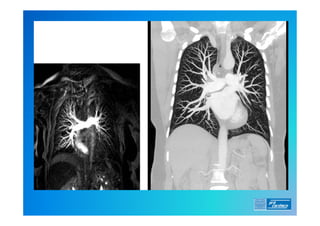

7) Angio TC

9) Angio RM

Diagnóstico . 0) EXAME FÍSICO 1)ECG (alterações frequentes ?) 2) RX de Tórax (o que esperar ?) 3) Laboratório (o que é importante ?) 4) D Dimero 5) Doppler Venoso MMII 6) Ecocardiograma (TT e TE) 7) Angio TC 8) Cintilografia Pulmonar (Ventilação/Perfusão) 9) Angio RM 10) Arteriografia